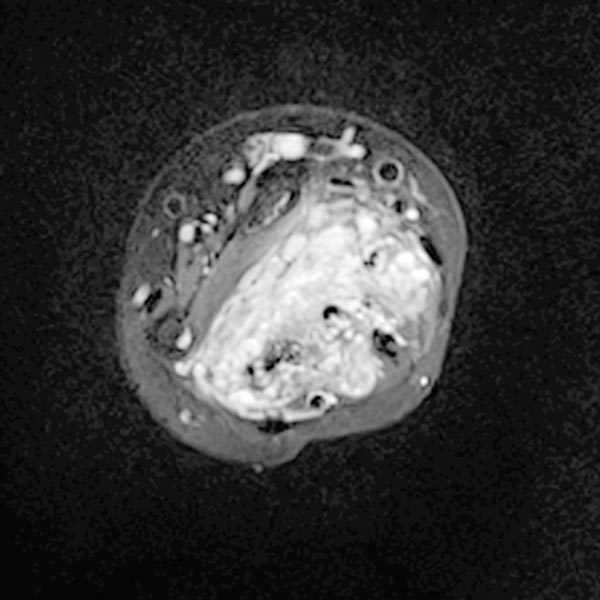

Axiale T1-gewichtete, fettunterdrückte KM-unterstützte Sequenz mittlerer Unterarm.

Die venöse Malformation reichert Kontrastmittel an innerhalb der durchsetzten Muskulatur.

Die Gefäßlumina der venösen Malformation sind jedoch relativ klein, es finden sich keine größeren tubulären Anteile.